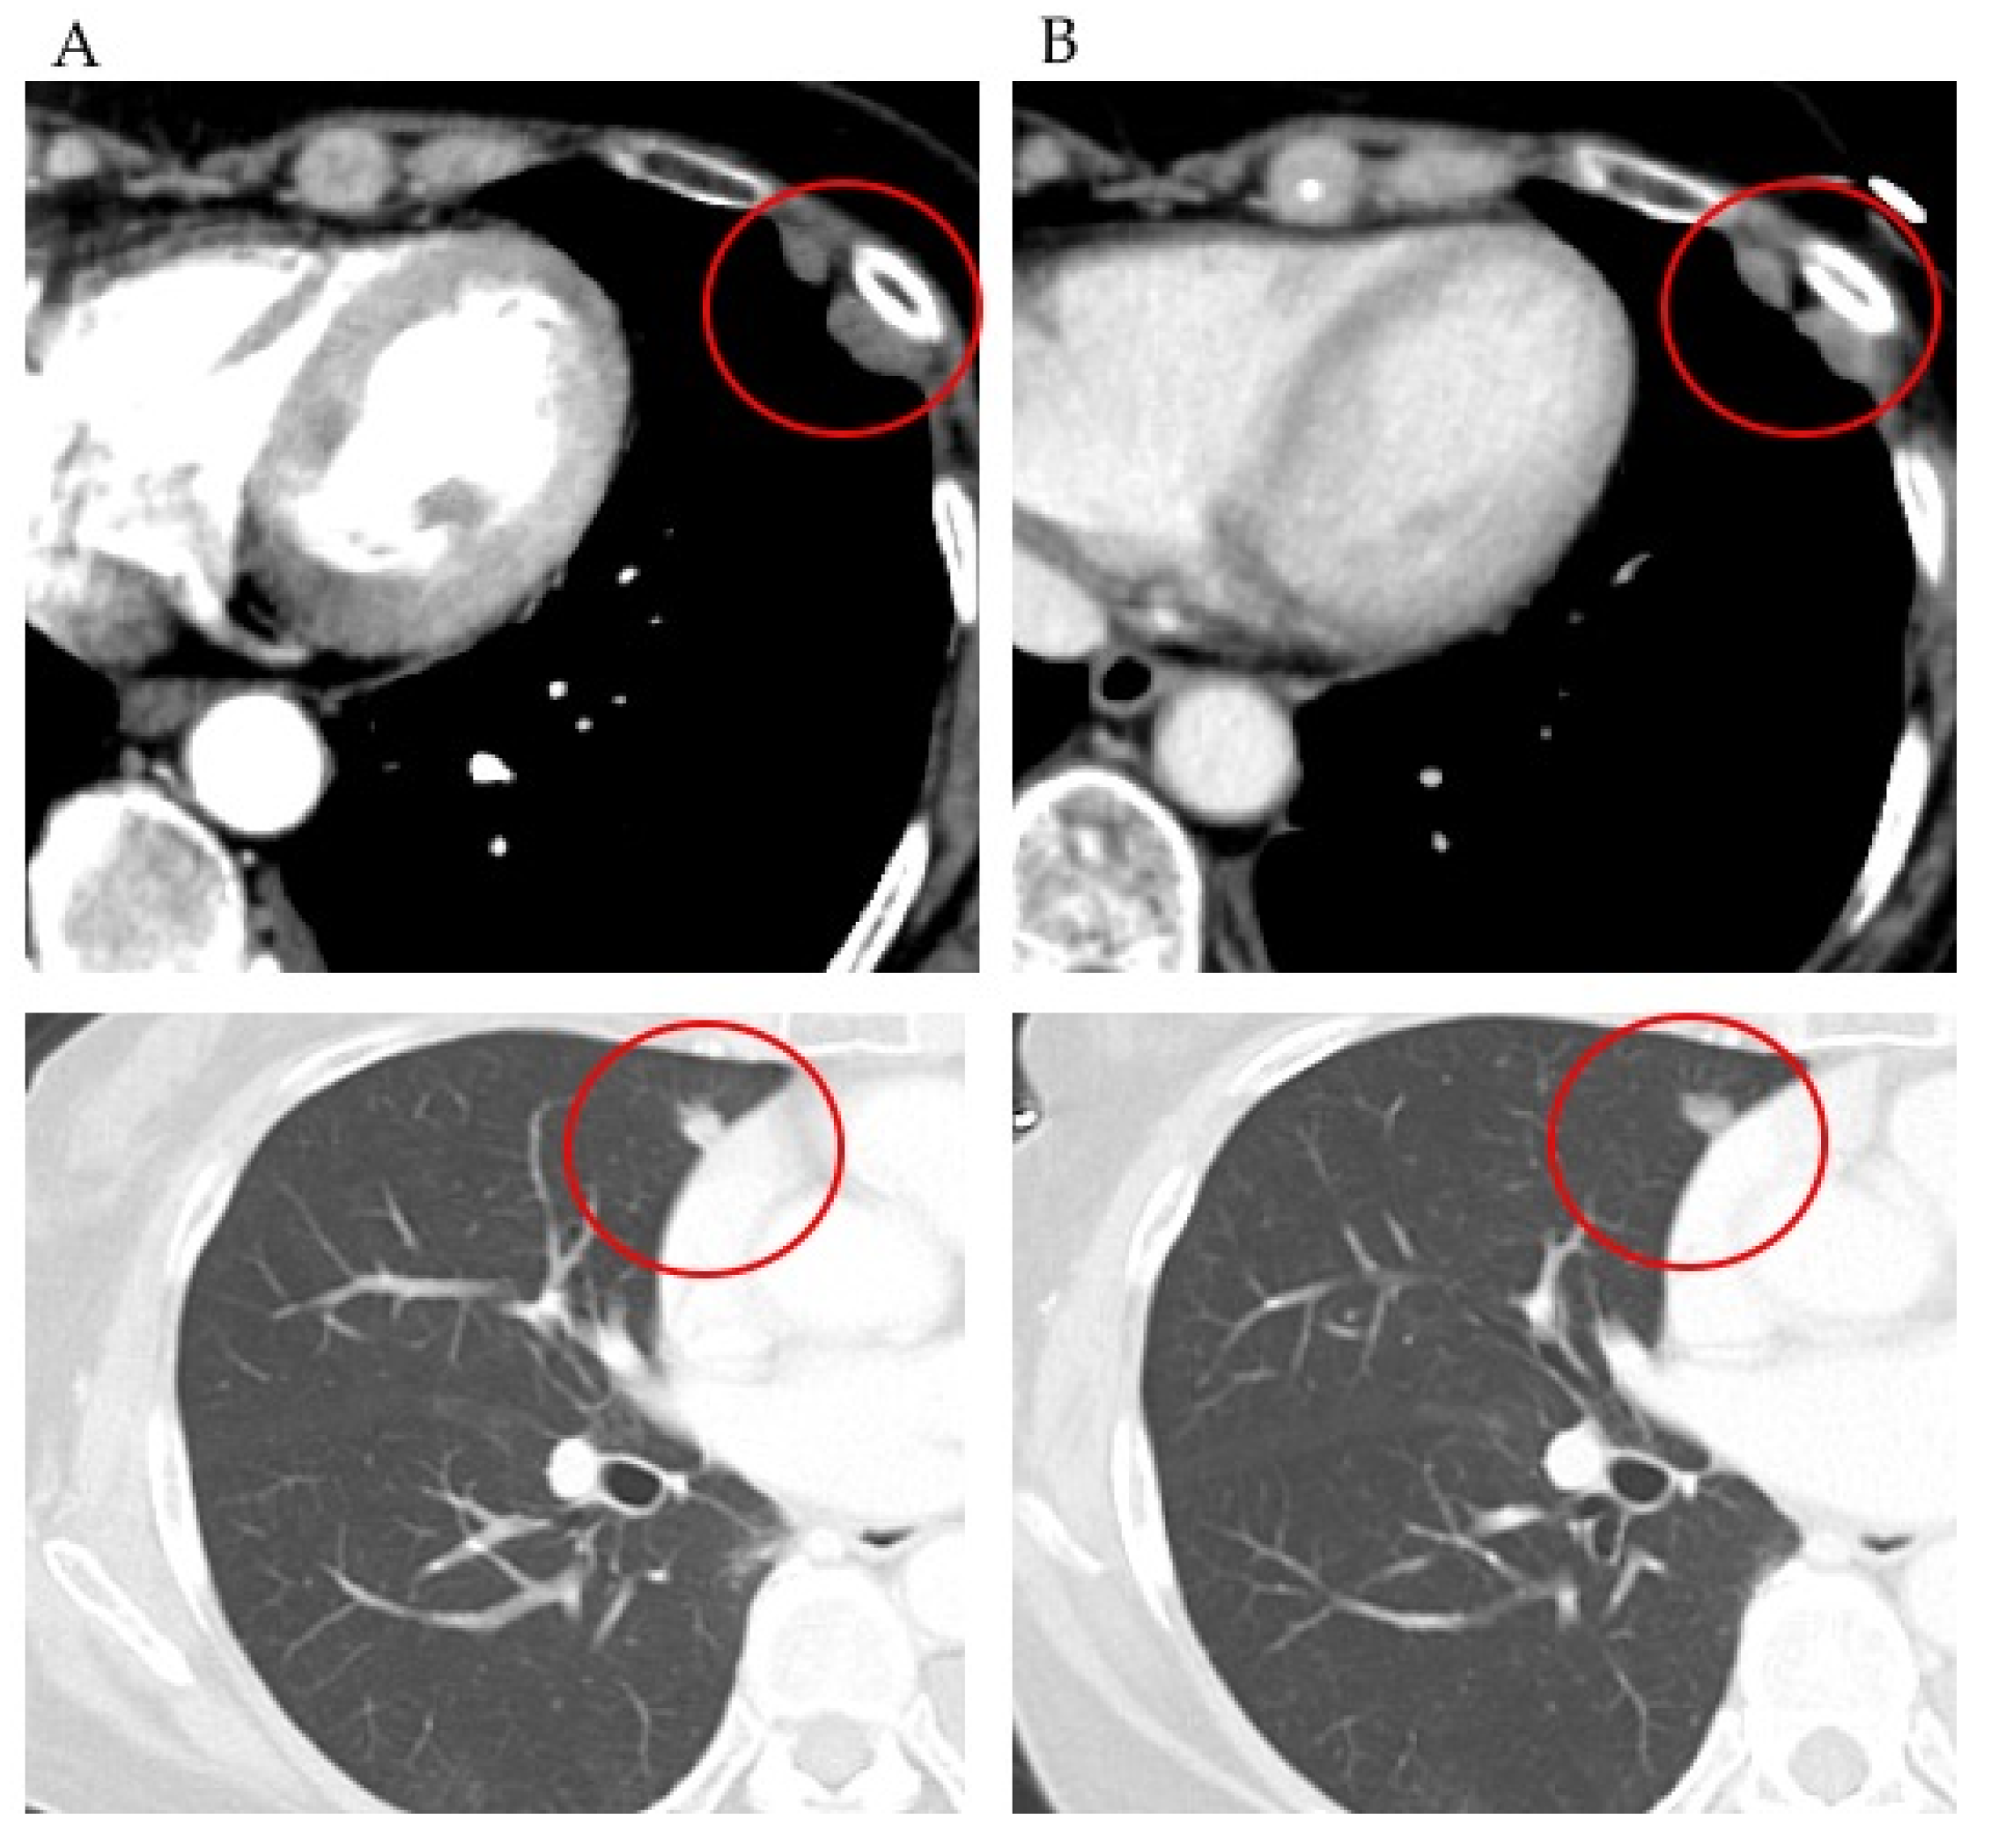

2.4.2. Case 2

2.4.3. Case 3